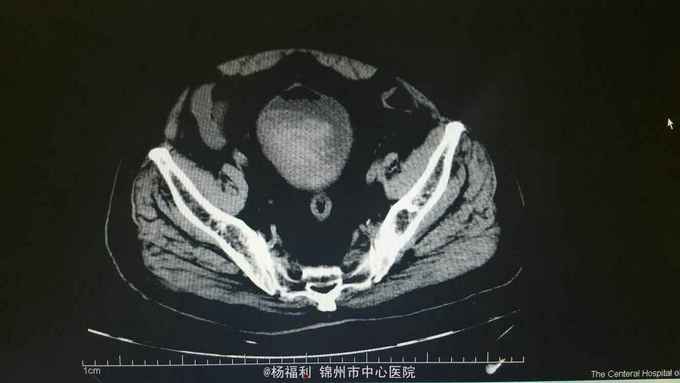

膀胱造瘘管内血尿伴血块,造瘘管周围窦口新鲜肉芽形成。耻骨上隆起,压痛阳性,扣诊浊音。 盆腔ct:见影像资料。内见大量血块。

尿潴留。膀胱内出血。膀胱造瘘术后。 给与患者留置尿管后行膀胱持续冲洗,血尿持续,于膀胱镜下给与患者清除膀胱内血块,发现造瘘口周围膀胱壁出血,滤泡样隆起,病理回报轻度不典型增生。电凝止血后回病房。